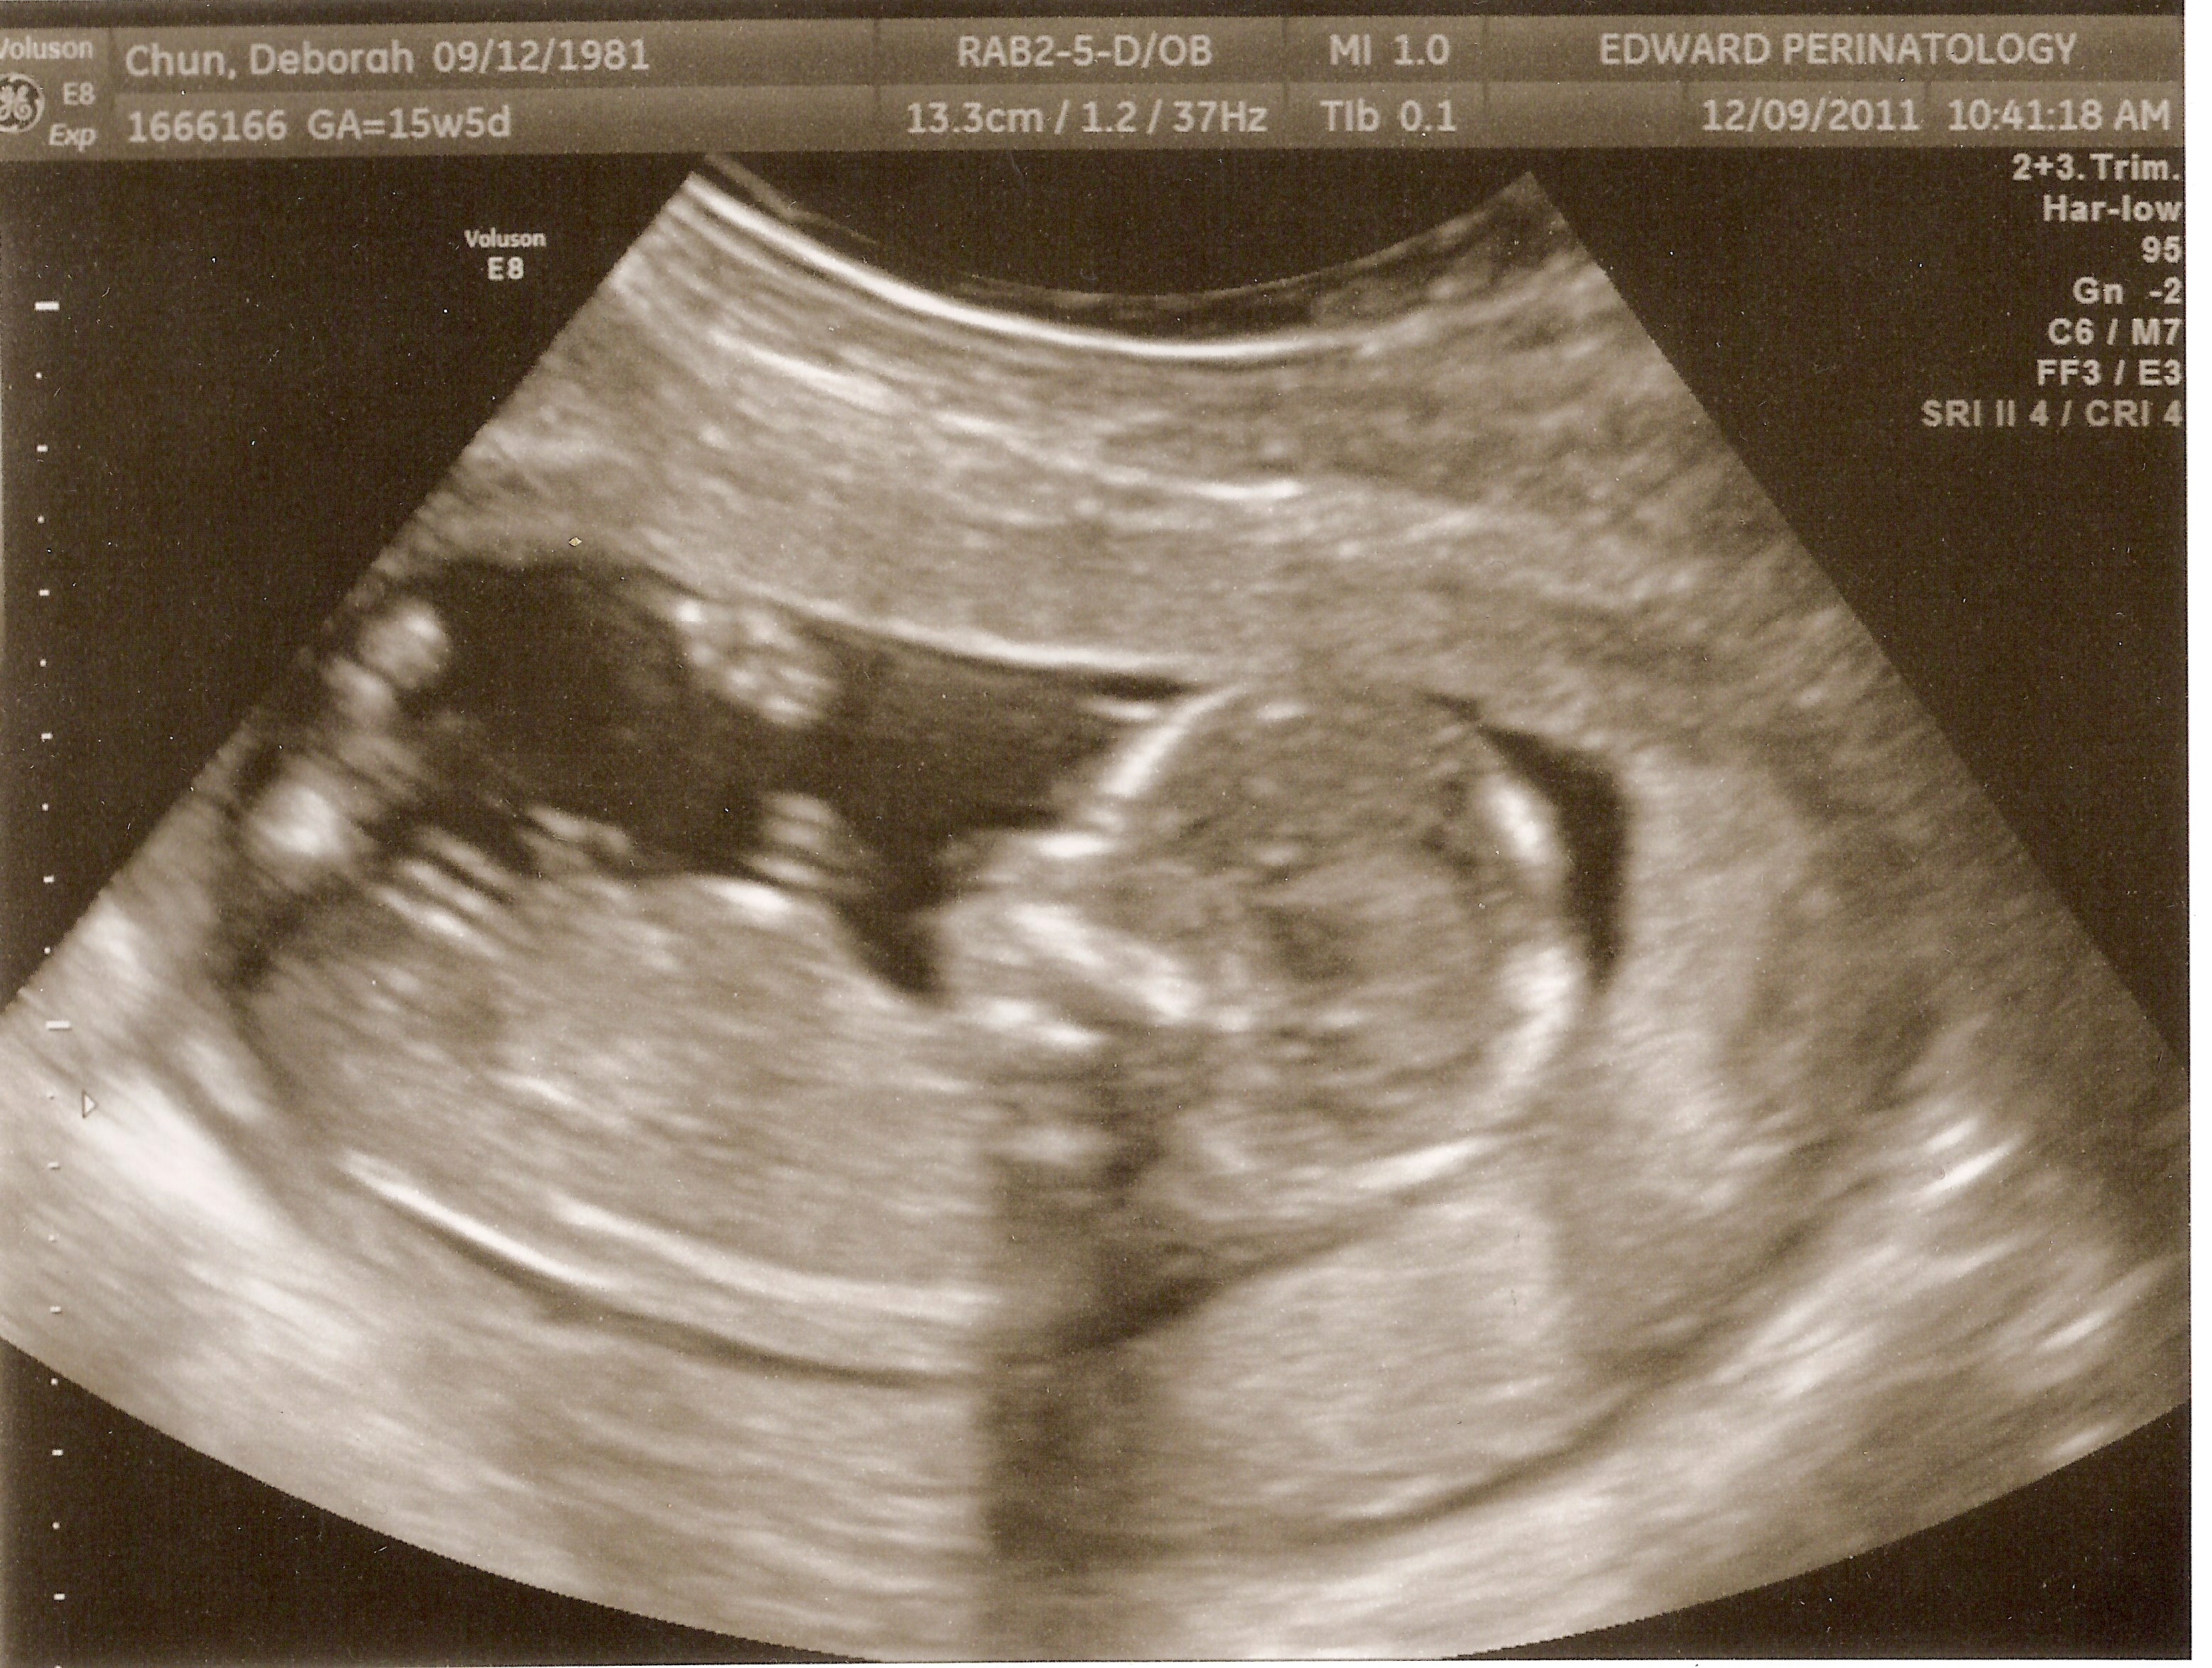

Throughout this pregnancy my doctors have been cautious. Not knowing the reasons I went into labor prematurely and delivered at 19 weeks last February 24 with our first child, Caleb, the doctors have seen me every two weeks with this pregnancy. When I went to my normal appointment on Friday at 21 weeks, 5 days, the ultrasound showed my cervix had shortened and was weak. The good news is that I was not in labor and that they’d be able to put in a cerclage to try and save as much length to my cervix as they could.